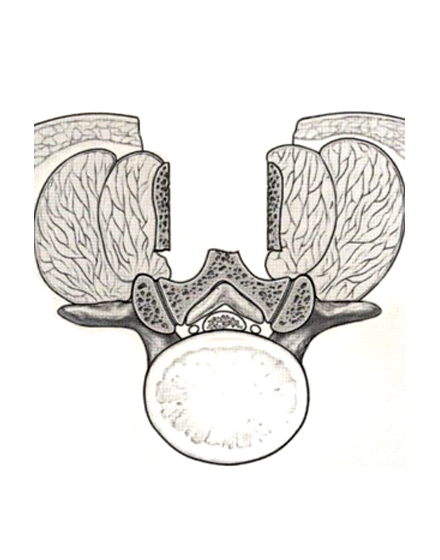

腰椎棘突起縦割式椎弓切除術

適応となる疾患:腰部脊柱管狭窄症、腰椎変性すべり症など

腰椎後方(背中)から椎弓、肥厚した黄色靭帯を切除し、硬膜管(馬尾神経の通っている管)の圧迫を解除します。棘突起を縦割することで腰背筋を骨から切離せず温存して、余分な組織のみ切除する低侵襲な手術を行います。従来の手術に比べ、術後の腰痛が軽度です。手術時間は1時間くらいで翌日から歩行が許可されます。入院期間は通常10~14日ぐらいになります。